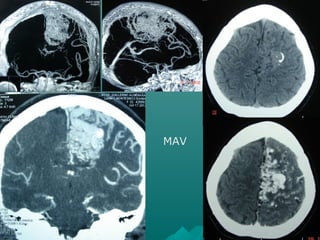

PROTOCOLO ANGIOGRAFIAPROTOCOLO ANGIOGRAFIA

CEREBRALCEREBRAL

 kV 80kV 80

 Effective mAs *Effective mAs *

 Slice collimation 1.0 mmSlice collimation 1.0 mm

 Slice width 1.25 mmSlice width 1.25 mm

 Rotation time 0.6 sec.Rotation time 0.6 sec.

 Kernel C30sKernel C30s

 Increment 0.8 mmIncrement 0.8 mm

 Image order ca-crImage order ca-cr

 Una distancia de 15 cm, tomará 8.3 segundosUna distancia de 15 cm, tomará 8.3 segundos

CEREBRAL *MILIAMPERAJECEREBRAL *MILIAMPERAJE

 EDAD kV mAs CTDIVolEDAD kV mAs CTDIVol

 < 6 years 80 80 6.5 mGy< 6 years 80 80 6.5 mGy

 6 years – 12 years 80 120 9.8mGy6 years – 12 years 80 120 9.8mGy

MAV